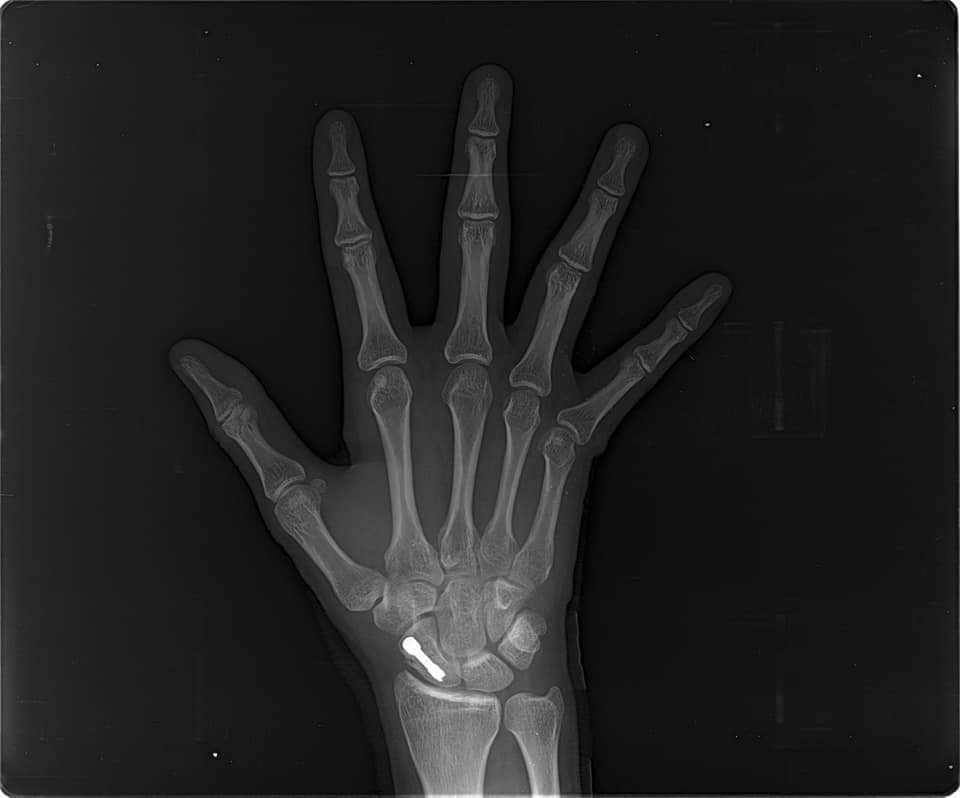

El Dr. Javier Severiche nuevamente dando soluciones a personas que requieren de su gran experiencia, en Clinica Trauma Clinic este sábado entró a cirugía para solucionar una fractura en la muñeca derecha de un paciente de 25 años.

Presenta una fractura de escafoides. Se realiza una osteosintesis con mini incision utilizando un tornillo de Herbert,logró una buena estabilización con buenos resultados.